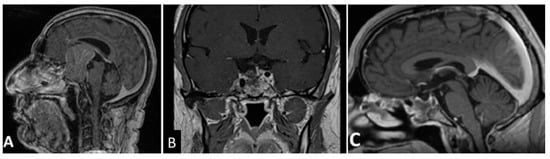

Among the 96 patients included, 55 were men (57.3%) and 41 were women (42.7%), and the mean age was 52.2 years (range 26–81 years). Gender and age were not significantly associated with EoR rate (p = 1.763) or hospital length of stay. Mean cranio-caudal diameter of lesion was 46.5 mm (range 41–61 mm). According to Knosp [8] grading scale, 30 (31.2%) were classified as grade 0; 24 (25.0%) grade 1; 19 (19.8%) grade 2; 9 (9.4%) grade 3 and 14 (14.6%) grade 4. Endocrinological screening confirmed the non-functioning status in all patients included in the study. Seventy-eight patients (81.2%) presented with visual field defects, 9 of whom (9.4%) also had visual acuity impairment. Fifty-three patients (55.2%) presented with various degree of anterior pituitary insufficiency: 27 had panhypopituitarism, 14 had combined corticotropic and thyrotropic insufficiency, 6 had isolated corticotropic insufficiency, 3 had isolated thyrotropic insufficiency and 3 isolated gonadotropic insufficiency. Twelve patients (12.5%) had headaches and 3 (3.1%) presented drowsiness associated with hydrocephalus. According to intraoperative assessment of lesion consistency, 50 GPAs (52.1%) were soft, whereas 46 GPAs (47.9%) were firm/fibrous. Thirty-one GPAs (32.3%) were deemed to have significant vascularization due to profuse intraoperative bleeding impairing visualization through the endoscopic lens and requiring more than 20 mL of advanced hemostatic matrix, whereas the remaining 65 GPAs (67.7%) did not. Interestingly, our results are in keeping with the data reported by previous studies [11,12], confirming that 2/3 of GPAs are not highly vascularized. EoR was classified as follows: GTR in 34 cases (35.4%) (Figure 1), NTR in 12 cases (12.5%) (Figure 2), and STR in 50 (52.1%) (Figure 3 and Figure 4).

Figure 2. T1- weighted contrast-enhanced coronal MR images. Preoperative view (A) showing a giant pituitary macroadenoma, Knosp grade 3. (B) Three-month postoperative view showing NTR with a small tumor residue in the medial left cavernous sinus (white asterisk).